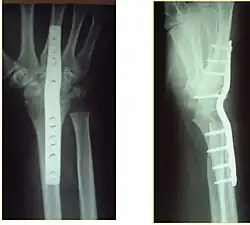

Surgery is generally indicated for displaced or unstable fractures.[18] The techniques of surgical management include open reduction internal fixation (ORIF), external fixation, percutaneous pinning, or some combination of the above. The choice of operative treatment is often determined by the type of fracture, which can be categorized broadly into three groups: partial articular fractures, displaced articular fractures, and metaphyseal unstable extra- or minimal articular fractures.[5]

Significant advances have been made in ORIF treatments. Two newer treatments are fragment-specific fixation and fixed-angle volar plating. These attempt fixation rigid enough to allow almost immediate mobility, in an effort to minimize stiffness and improve ultimate function; no improved final outcome from early mobilization (prior to 6 weeks after surgical fixation) has been shown. Although restoration of radiocarpal alignment is thought to be of obvious importance, the exact amount of angulation, shortening, intra-articular gap/step which impact final function are not exactly known. The alignment of the DRUJ is also important, as this can be a source of a pain and loss of rotation after final healing and maximum recovery.

If the fractures are unlikely to be reduced by closed means, open reduction with internal plate fixation is preferred.[5] Although major complications (i.e. tendon injury, fracture collapse, or malunion) result in higher reoperation rates (36.5%) compared to external fixation (6%), ORIF is preferred, as this provides better stability and restoration of the volar tilt.[5][23] Following the operation, a removable splint is placed for 2 weeks, during which time patients should mobilize the wrist as tolerated.[5]